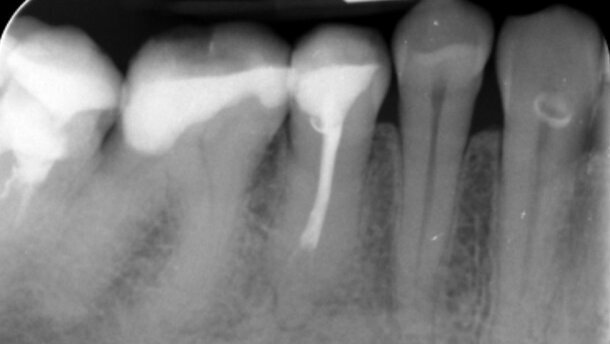

Do mojej praktyki zgłosiła się pacjentka G.B. lat 59, skarżąc się na dolegliwości bólowe okolicy zęba 44. Wykonałam zdjęcie RVG: kanał zęba niedopełniony, widoczna rozpoczynająca się resorbcja zewnętrzna (Ryc. 1). Z powodów opisanych powyżej zastosowałam leczenie konwencjonalne. Użyłam endodontycznej kątnicy Dentaport Tri Auto ZX i narzędzi rotacyjnych, systemów płuczących z werseniem sodu. Niestety, kanał był jak zamurowany. Na 24 godz. założyłam wkładkę z EDTA. Kolejna wizyta i znowu bezskuteczna próba udrożnienia mechanicznego (Ryc. 2).

Sięgnęłam więc po laser LightWalker erbowo-jagowy – założyłam końcówkę kontaktową Precisio 300/14 (niestety, nie użyłam końcówki PIPS, bo jej jeszcze nie posiadam, a pewnie byłaby to dla mnie końcówka z wyboru). Ustawiłam następujące parametry: tryb MPS 250 mJ, 20 Hz. Jeden impuls: pacjentka poczuła nieznaczny ból, a kanał był już udrożniony (Ryc. 3). Wypełniłam kanał (Ryc. 4), a dolegliwości bólowe się skończyły.